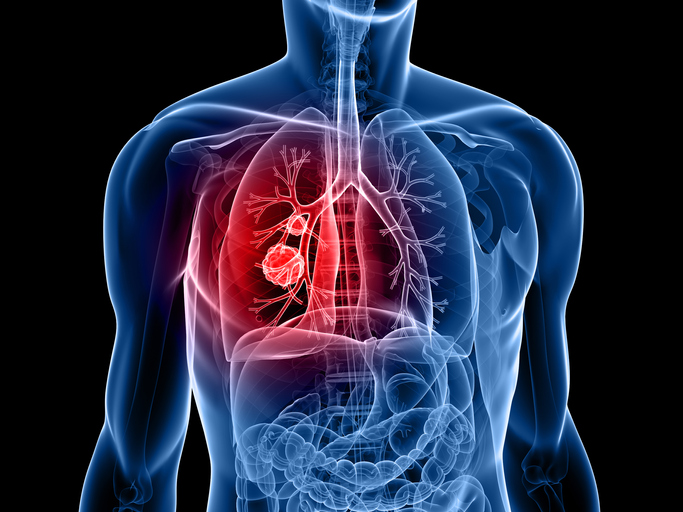

폐암은 원발성 폐암을 말하며 원발성 폐암은 폐에서 기원하는 악성 종양을 말한다. 폐로 전이된 암은 폐로 전이된 것으로 분류되며, 폐암이라기 보다는 기원 장기로 전이된 것으로 분류된다. 폐암은 조직학적 유형에 따라 크게 소세포폐암과 비소세포폐암으로 분류된다.

이 분류의 이유는 소세포 폐암이 치료 및 예후 측면에서 다른 유형의 폐암과 확연히 다른 특징을 가지고 있기 때문입니다.

이러한 폐암의 원인으로 인해 폐암으로 진단되기 전에 폐암 초기증상을 조기에 발견하면 다른 장기로의 전이나 진행성 폐암으로의 진행을 어느 정도 지연시키거나 적절하게 치료할 수 있지만 일반적으로 폐암의 초기 단계는 특별한 징후나 증상이 없으므로 조기에 발견하는 경우는 극히 드뭅니다.